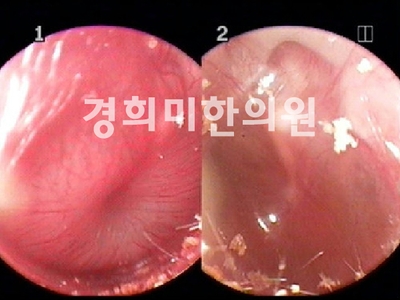

경희미의원 진단, 치료를 먼저 10세 여아의 급성 비염 비내시경 치료 전후 사진을 소개합니다.

치료전(좌) → 치료후(우) 여 / 10세, 급성 비염, 2주 치료기간

비염은 정확한 진단이 우선입니다.급성 및 만성 비염, 축농증, 알레르기 비염의 경우 증상이 다를 뿐만 아니라, 코의 내시경 검사 코 점막과 콧물의 양상도 다릅니다.그리고 중이염 여부도 확인해 보도록 합시다.경희미의원은 조재훈 원장이 직접 코내시경을 통해 코 점막의 상태를 확인합니다.주요 치료는 면역 관련 한약이기 때문에 빈번하게 병원을 방문할 필요가 없습니다.